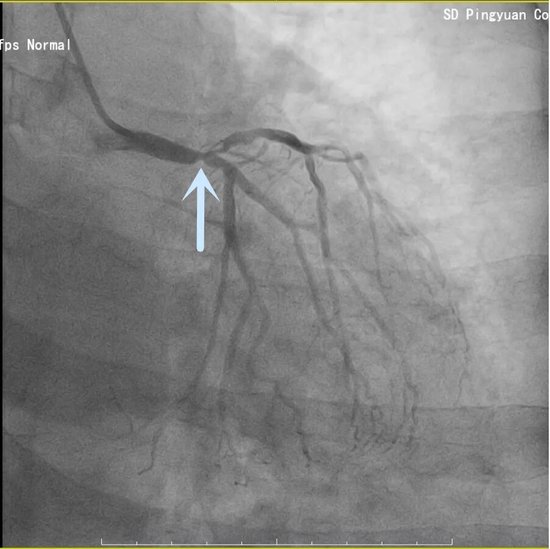

61岁的李阿姨因“胸闷1天,加重1小时”紧急入院,确诊为急性下壁心肌梗死。心内科介入团队迅速响应,一键启动导管室。急诊冠脉造影显示:冠心病三支病变——这意味着患者的三条主要血管均存在严重狭窄或闭塞,病情极为危重。

面对复杂病变,介入团队凭借丰富经验,迅速锁定“罪犯血管”右冠状动脉。在纤细的血管腔内,导丝精准通过闭塞段,球囊扩张、支架植入一气呵成。术后造影显示,血流瞬间恢复畅通,患者胸痛症状随即缓解。这场手术的成功,不仅体现了团队的应急反应速度,更考验了术者在多支病变中准确判断责任血管的“火眼金睛”。